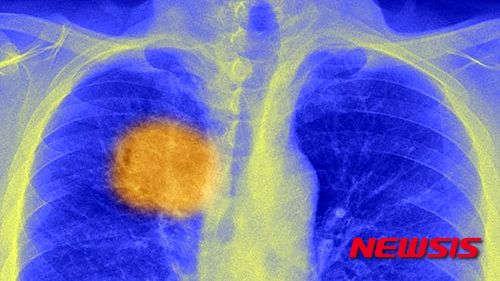

【서울=뉴시스】박상주 기자 = 암을 정복할 수 있는 ‘아킬레스 건’이 발견됐다. BBC방송과 텔레그래프 등은 4일(현지시간) 면역 체계가 암의 핵심을 공격할 수 있는 종양 내 특별한 표식을 찾아냈다고 보도했다.

영국 유니버시티칼리지런던(UCL)과 영국암연구소(ICR) 과학자들은 암세포에 나타나는 공통점을 찾기 위해 암 환자 수백 명을 분석한 결과 모든 종양이 변화하지 않는 특정한 항원 형태의 분자를 지니고 있음을 밝혀냈다. 항원이란 인체 면역체계가 적으로 인지해 반응을 하게 만드는 물질이다. 연구진들은 이번 발견은 암 치료의 신기원을 열 수 있는 획기적인 방안이며, 앞으로 2년래 이를 이용한 새로운 치료법이 나올 것이라고 전망했다.

연구의 주역 중 하나인 찰스 스원턴 UCL 교수는 BBC방송과의 인터뷰에서 “이젠 모든 세포에 존재하는 종양 항원을 식별해 이를 제거할 수 있게 됐다. 이들은 암의 아킬레스건에 해당된다”며 “정말 짜릿하다. 이젠 환자별 맞춤형 처방으로 암치료의 절대적인 한계를 넘어설 수 있게 됐다”라고 말했다.